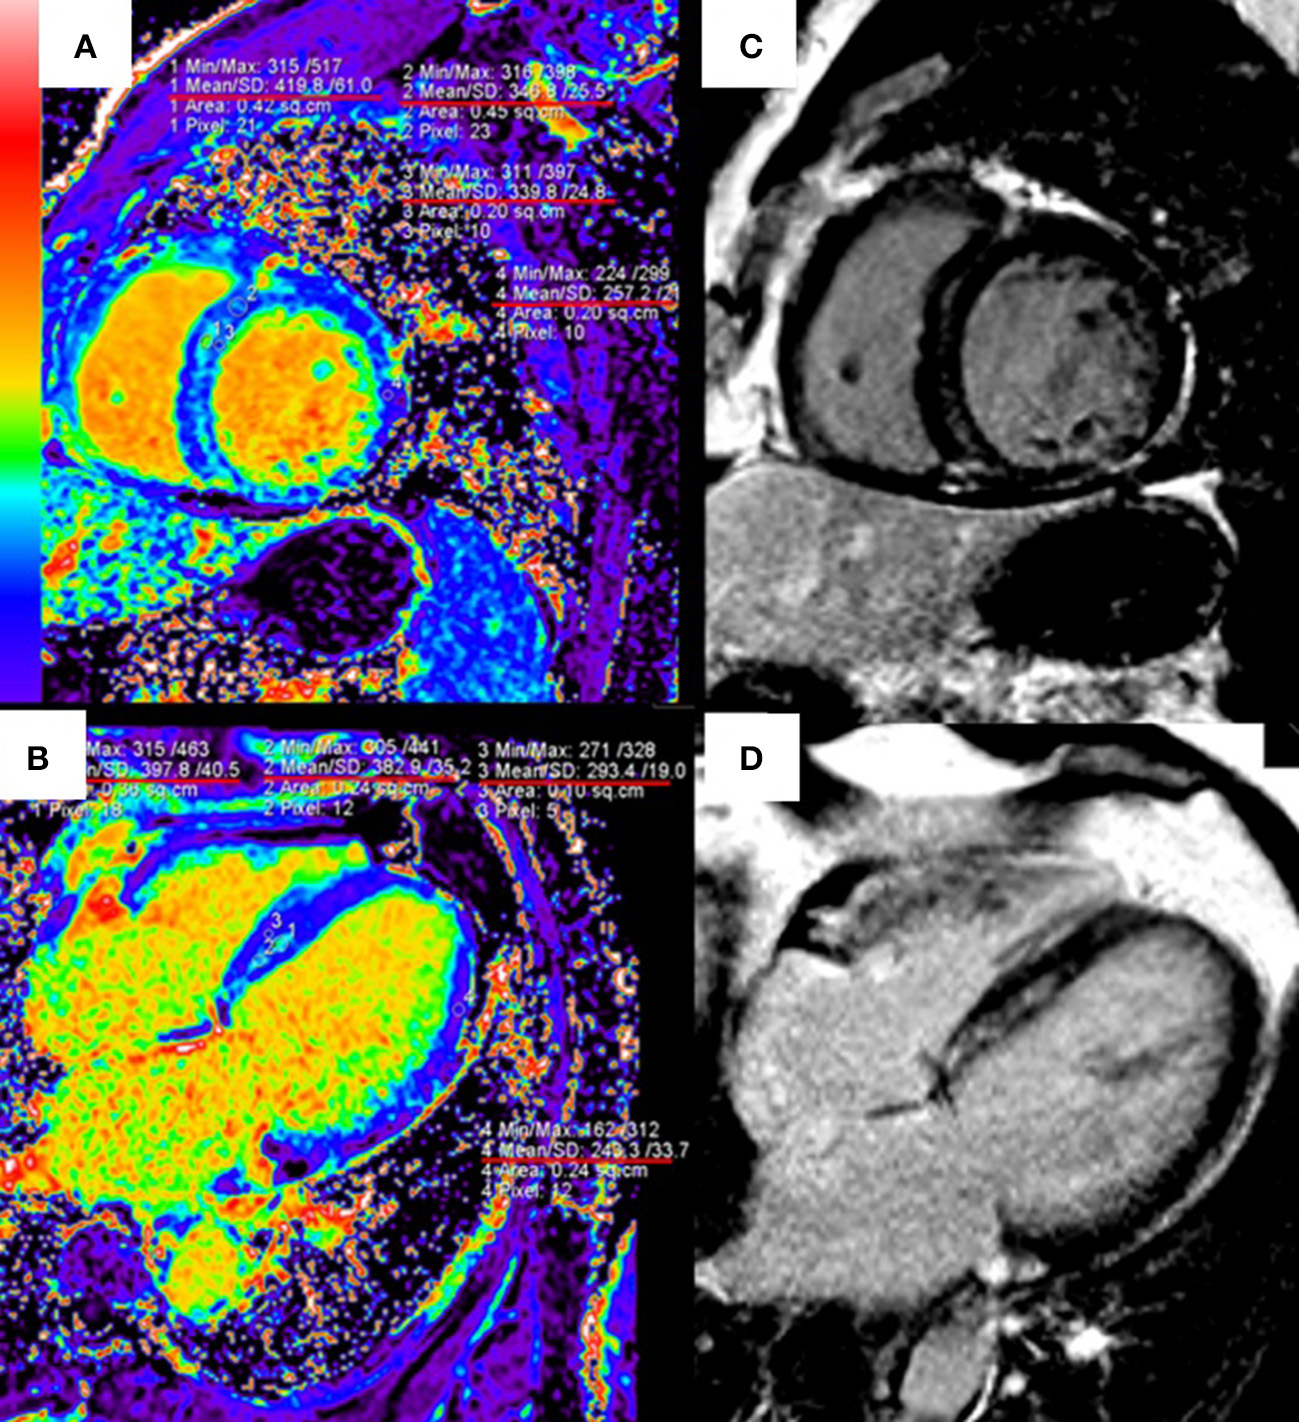

T1 mapping and ECV are useful to quantify the infarct size and the extent of “gray zone” in ischemic cardiomyopathies. The early CMR imaging with T1 mapping and ECV is also a potent diagnostic tool for identifying the etiology of MI with non-obstructive coronary arteries (118). In patients with nonischemic cardiomyopathies such as HCM and DCM, native T1 and ECV have shown strong diagnostic and prognostic values, especially for patients without LGE (9, 119). ECV can identify diffuse myocardial fibrosis at the early stage of hypertensive cardiomyopathy, before the appearance of LGE (120) (Figure 2). T1 mapping is also included in the updated Lake Louise Criteria (CMR consensus recommendations for myocarditis) in 2018 to detect edema and reactive fibrosis during the early inflammatory phases (121) and it can significantly improve the diagnostic ability of CMR for acute myocarditis (122).

Figure 2

Quantitative extracellular volume (ECV) fraction images [left column, (A,B)] and late gadolinium enhancement (LGE) [right column, (C,D)] in a hypertension patient. The abnormal ECV region is larger than LGE. Reprinted with permission from Wang et al. (120).